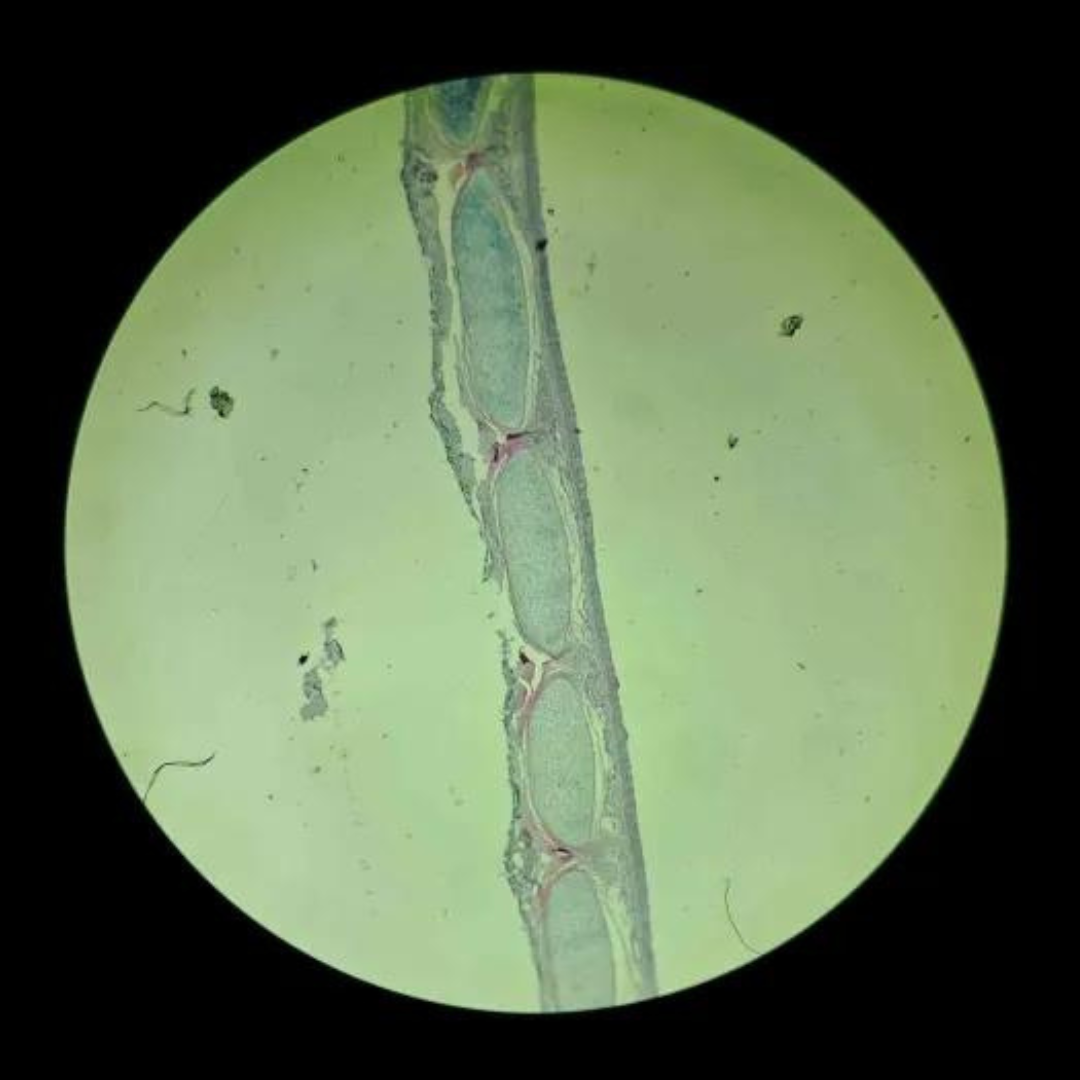

Bone

Bone

Bone

Bone

Bone